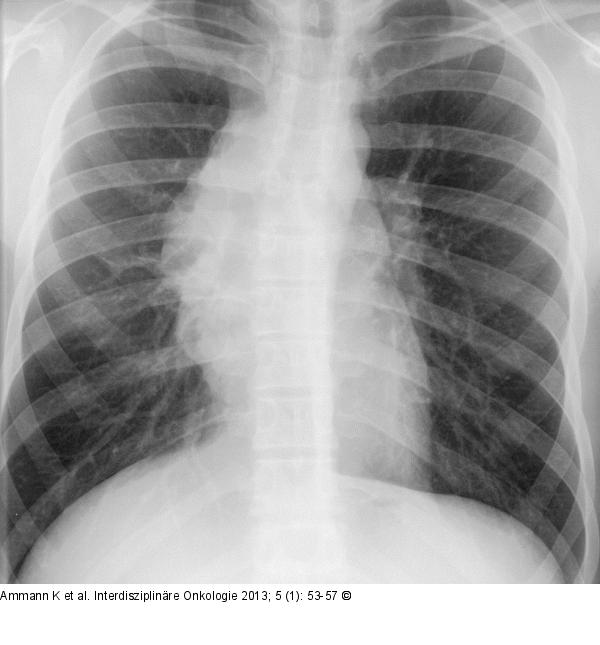

Abbildung 1: Thoraxröntgen Thoraxröntgen eines 18-jährigen Patienten mit mediastinaler Verschattung. |

Thoraxröntgen eines 18-jährigen Patienten mit mediastinaler Verschattung. |